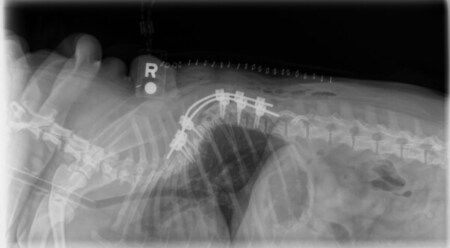

Canine Vertebral Stabilization

専門医レベルの講演と座談会:トピックには、頭蓋内手術、頭蓋再建、低侵襲神経外科手技、脊椎の生体力学、インプラント選定の判断基準、比較神経外科戦略、ならびに腰仙部手術の最新動向が含まれます。